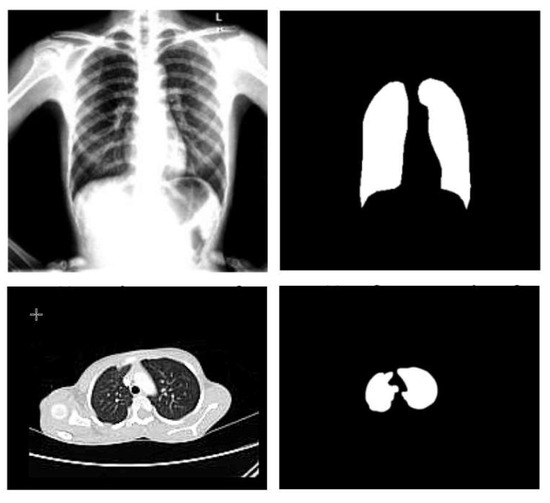

- Normalization: To improve the convergence of the training phase, input pixels to any AI system must have a normalized data distribution. To normalize an image, the distribution’s mean value is first subtracted from each pixel, then divided by the result by the standard deviation. Sample X-ray and CT images are shown in Figure 2 before (on the left) and after (on the right) the preprocessing steps.

3.1.3. Segmentation